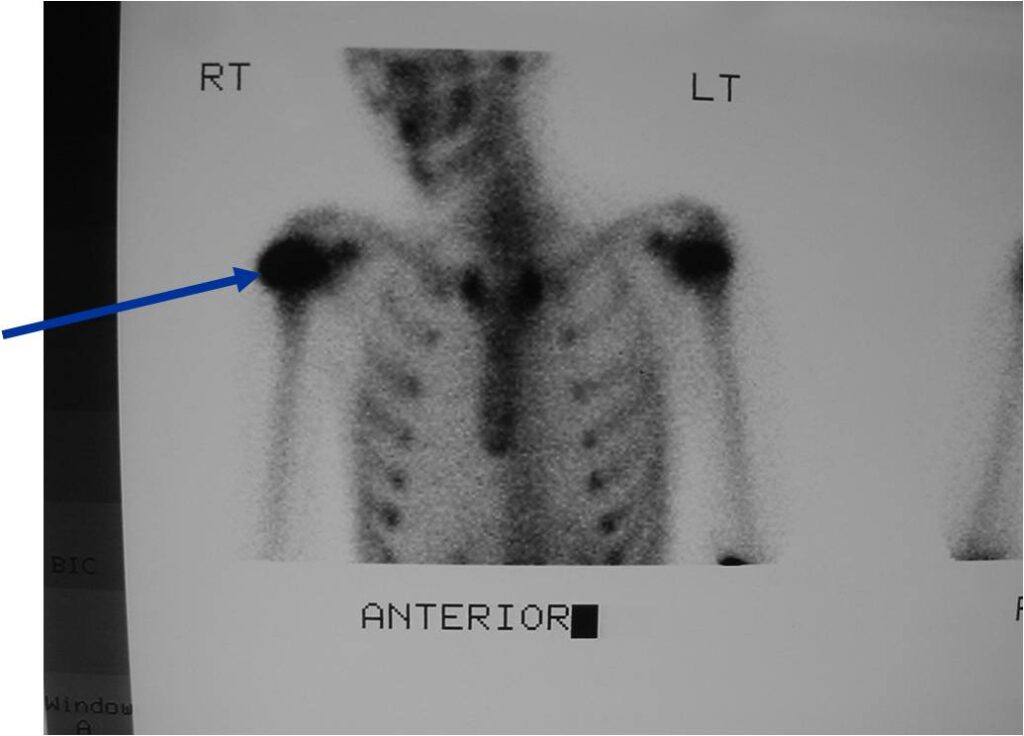

Bone scan: Chondroblastomas demonstrate intense increased uptake on a bone scan